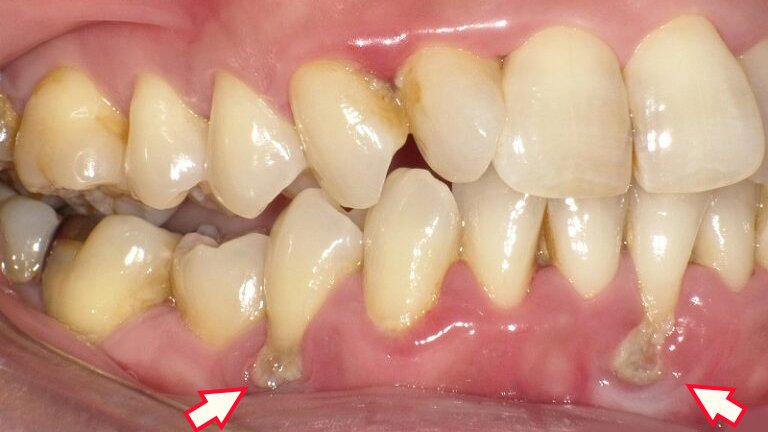

当院は、歯周病および重度歯周病の治療に特化した専門的な歯科医院です。最新の歯槽骨再生療法をはじめ、歯周外科・フラップ手術や3DS除菌療法など、多岐にわたる治療法をご提供しています。

熟練した歯科衛生士によるメインテナンスや歯石除去により、日常的なケアも万全です。さらに、歯周内科治療や遺伝子診断を取り入れ、個々の患者様に最適な治療プランを提供します。